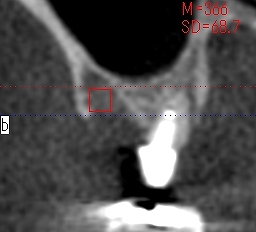

骨密度を測ります

骨の硬さを把握していきます

上顎洞までの距離はしっつかりとあるわけでもありません